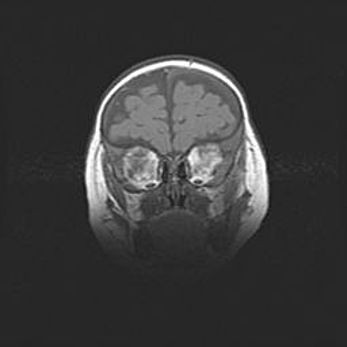

Множественные кисты обоих полушарий головного мозга, наибольшая из них в правой затылочной области. Ассиметричная атрофическая гидроцефалия.

Возраст: 7 месяцев

Вес: 5660 г

Пол: мужской

Окружность головы: 41,5 см

Срок гестации: 28-29 недель

Кисты головного мозга развиваются в результате многоочаговых некрозов вещества мозга и возникают вследствие перенесенной перинатальной инфекции, менингитов, энцефалитов, асфиксии, родовой травмы, расстройств мозгового кровообращения различного генеза. Образованию кист в веществе головного мозга плодов и новорожденных способствуют такие факторы, как высокое содержание в нем воды, недостаточная (или отсутствие) миелинизация и слабая астроглиальная реакция на повреждение.

Кисты могут сочетаться с гидроцефалией и другими поражениями головного мозга.